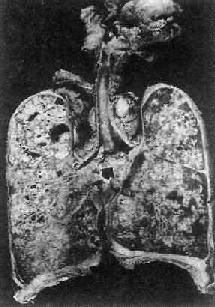

2)肺粟粒性结核病:又称血行播散型肺结核病。急性粟粒性肺结核病常是全身粟粒性结核病的一部分。偶尔,病变也可仅局限于两侧肺内。这是由于支气管周围肺门或纵隔淋巴结干酪样坏死破入附近的静脉(如无名静脉、颈内静脉、上腔静脉),含大量结核菌的液化物经右心和肺动脉播散至双肺所引起。肉眼观,双肺充血,重量增加,切面暗红,密布灰白或灰黄色粟粒大小的结节,微隆起于切面(图18-7),并显露于肺膜表面。

图18-7 肺粟粒性结核病

图中白色点状病灶为粟粒性结核灶